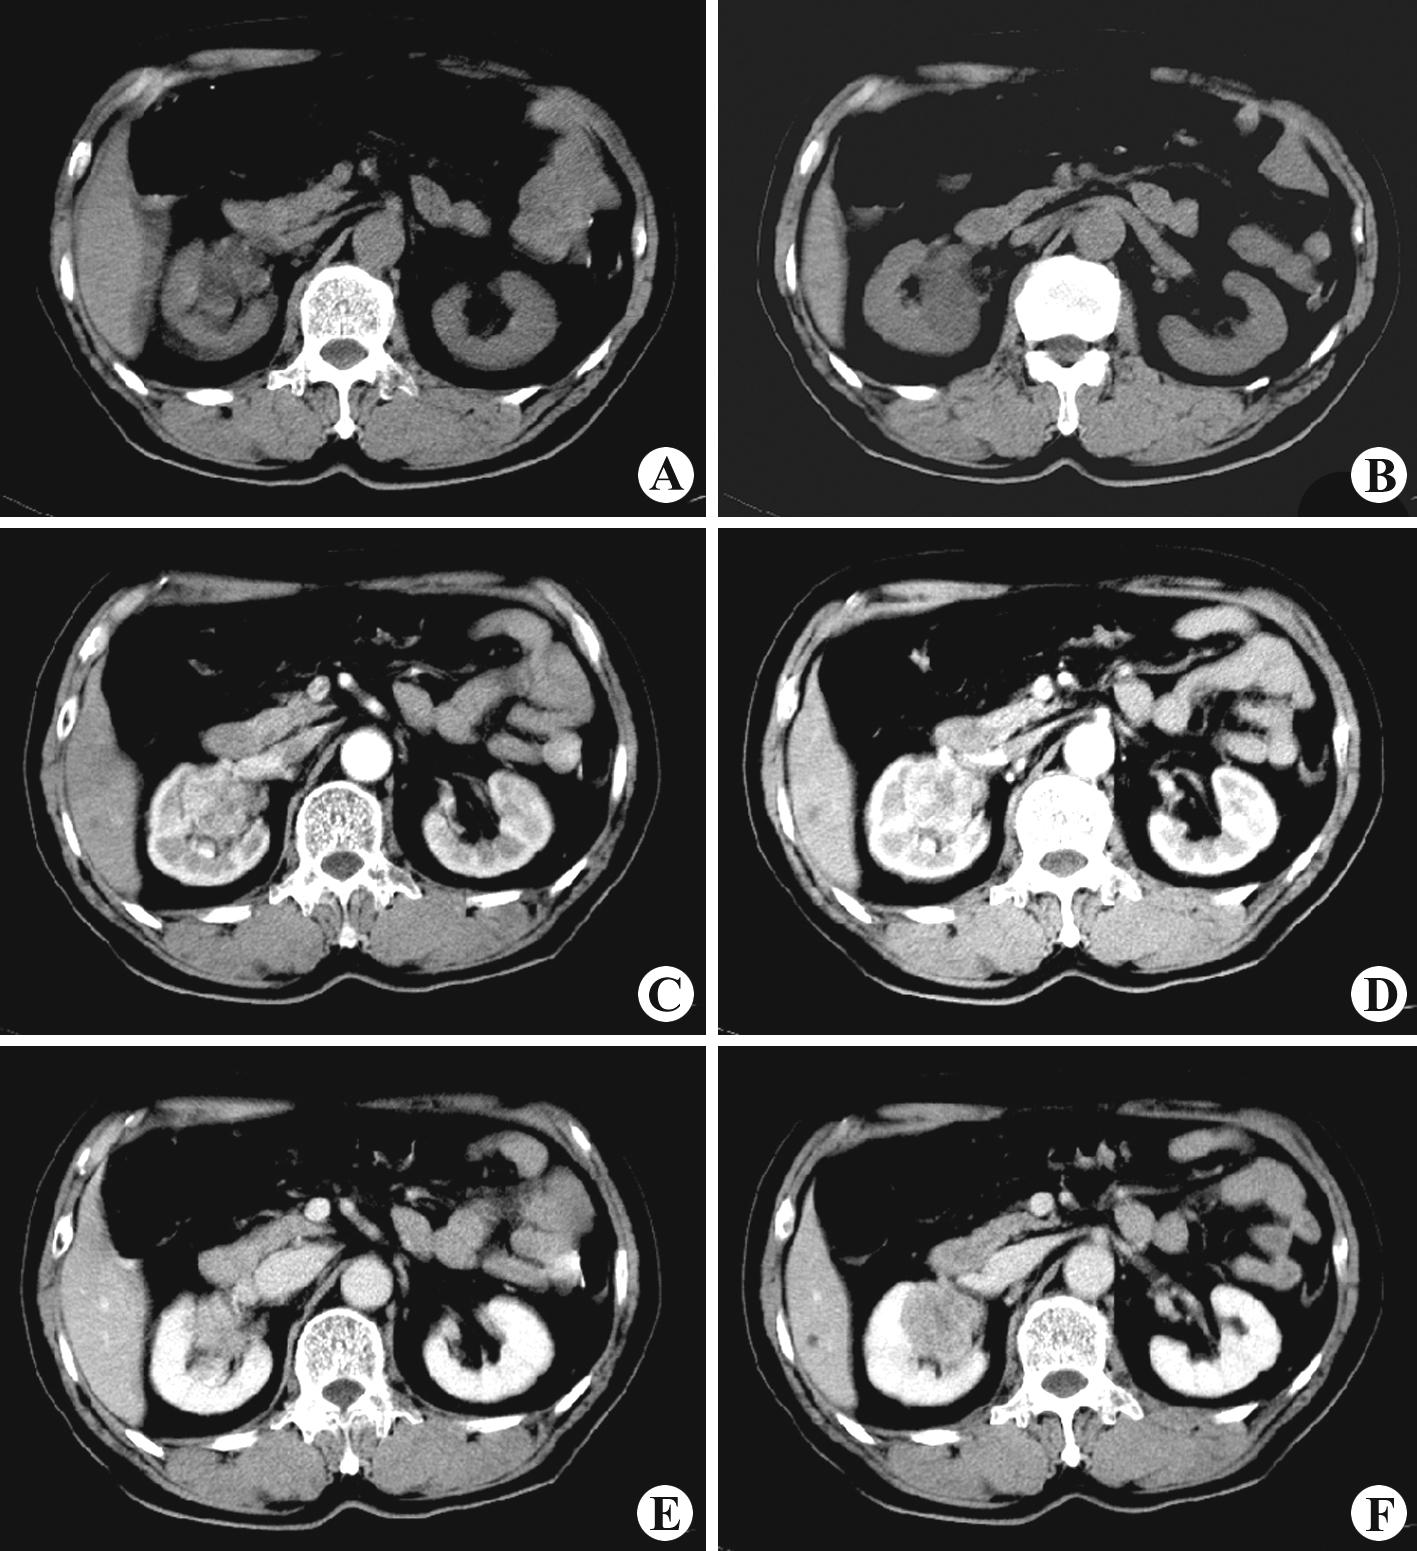

ct平扫(a,b)示双肾变形,略呈分叶状,密度不均匀,内见厚壁囊状低密度区

f)呈低密度,低于正常肾实质,显示更加清楚图6-129:右肾盂癌ctct平扫

图6-129:右肾盂癌ctct平扫(a,b)示右肾盂,肾窦内可见一不规则团块状软